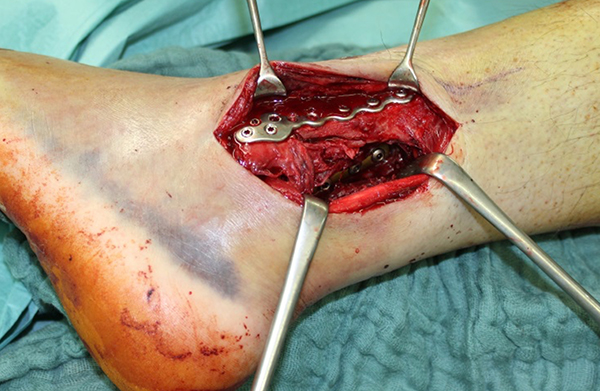

Die Versorgung von AO 44-B Frakturen erfolgt über einen längsverlaufenden lateralen Zugang. In der Regel gelingt eine suffiziente Stabilisierung mittels interfragmentärer Zugschraube (bei langem Frakturverlauf ggf. 2 Zugschrauben) und einer zusätzlichen Neutralisationsplatte (Abbildung 9 & 10).

Bei multifragmentären Frakturen (AO 44-B2.3) oder bei schlechter Knochenqualität sollte die Versorgung mittels winkelstabiler Plattenosteosynthese erwogen werden (Abbildung 11 & 12).